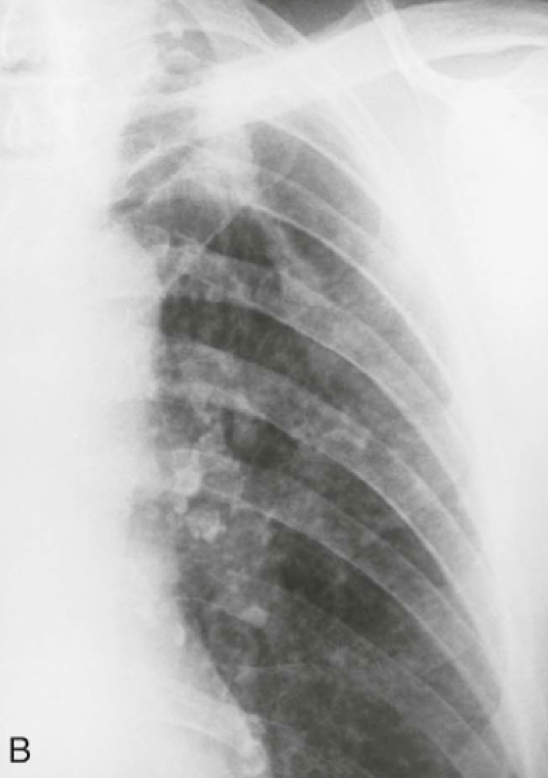

Question 15

Question

In what disease will you see this in?

Answer

• Pneumocystis jiroveci

• Silicosis

• Kaposi's Sarcoma

• Sarcoidosis